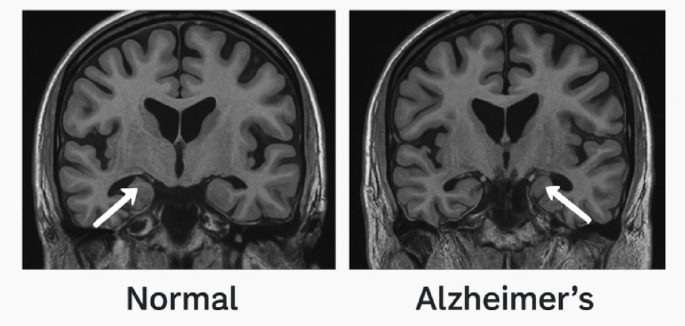

Participants were evaluated using the National Institute on Aging and Alzheimer’s Association (NIA-AA), diagnostic criteria for AD19, which were based on a comprehensive assessment including medical history, cognitive testing (MMSE < 24 or MoCA < 26), neuroimaging (MRI showing hippocampal atrophy), and biomarker analysis (elevated amyloid-beta and tau levels). Diagnosis was made by a board-certified neurologist to ensure clinical validity.

For neuroimaging, an MRI Scan for Hippocampal volume (2.0-4.5 mL), cortical thickness (1.8–3.2 mm) was done for AD progression tracking at the enrollment phase and end of study. Figure 2.

The box plots comparing cortical thickness, MoCA scores, MMSE scores, and hippocampal volume between the two groups reveal a stark contrast. AD cases consistently exhibit lower values across all metrics, with statistically significant differences (p = 0.0000), confirming that neurodegeneration is more pronounced in AD patients. Cortical thinning is visibly more severe in AD cases, supporting the well-established link between cortical atrophy and cognitive impairment in Alzheimer’s disease. Figure 5. Similarly, the lower MoCA and MMSE scores among AD participants reflect a decline in cognitive function, consistent with previous studies emphasizing the progressive nature of AD. The hippocampal volume comparison further reinforces these findings, as AD cases exhibit notable hippocampal atrophy, which aligns with the characteristic memory loss seen in the disease. Figure 5.